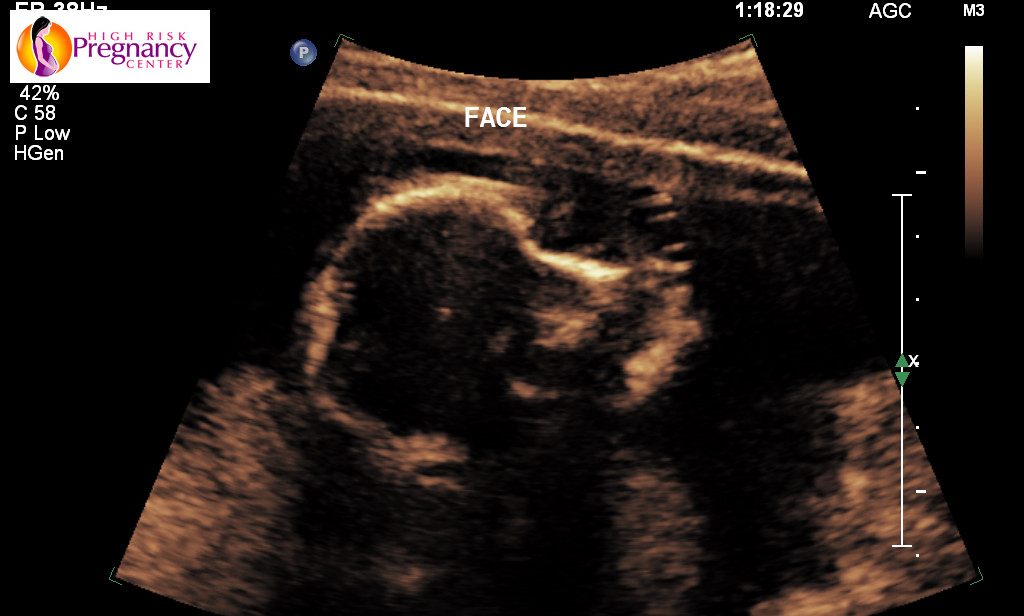

Over the next few weeks she had my wife come in to make sure everything was going okay which it has been. Since the OB only had a small little portable ultrasound machine all we could see was the baby on a screen about the size of an iphone plus maybe a little smaller. We now had our first legit ultrasound where we got to actually see a little demon face on the baby lol

see.They moved our due date up from the 27th of September to the 18th. It didn’t seem like much of a difference but it that moved it up by almost two more weeks.